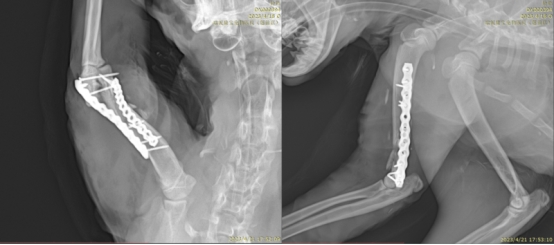

瑞派明星专科:精工修复,重建生命行动基石当爱宠不愿奔跑、拒绝跳跃,甚至因疼痛而退缩——这往往是肌肉骨骼系统发出的求救信号